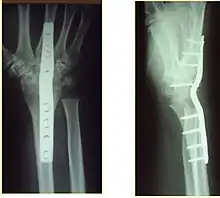

Surgery

Surgery is generally indicated for displaced or unstable fractures.[18] The techniques of surgical management include open reduction internal fixation (ORIF), external fixation, percutaneous pinning, or some combination of the above. The choice of operative treatment is often determined by the type of fracture, which can be categorized broadly into three groups: partial articular fractures, displaced articular fractures, and metaphyseal unstable extra- or minimal articular fractures.[5]

Significant advances have been made in ORIF treatments. Two newer treatments are fragment-specific fixation and fixed-angle volar plating. These attempt fixation rigid enough to allow almost immediate mobility, in an effort to minimize stiffness and improve ultimate function; no improved final outcome from early mobilization (prior to 6 weeks after surgical fixation) has been shown. Although restoration of radiocarpal alignment is thought to be of obvious importance, the exact amount of angulation, shortening, intra-articular gap/step which impact final function are not exactly known. The alignment of the DRUJ is also important, as this can be a source of a pain and loss of rotation after final healing and maximum recovery.

If the fractures are unlikely to be reduced by closed means, open reduction with internal plate fixation is preferred.[5] Although major complications (i.e. tendon injury, fracture collapse, or malunion) result in higher reoperation rates (36.5%) compared to external fixation (6%), ORIF is preferred, as this provides better stability and restoration of the volar tilt.[5][23] Following the operation, a removable splint is placed for 2 weeks, during which time patients should mobilize the wrist as tolerated.[5]